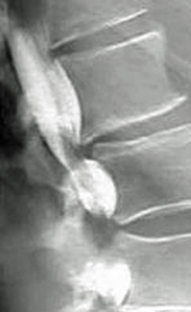

Which of the following imaging techniques illustrated in the pictures would be the most efficient to discover if there is a nerve root compression at the L4 level?

Q16: Which of the following imaging techniques illustrated

Q17: Which of the following imaging techniques illustrated